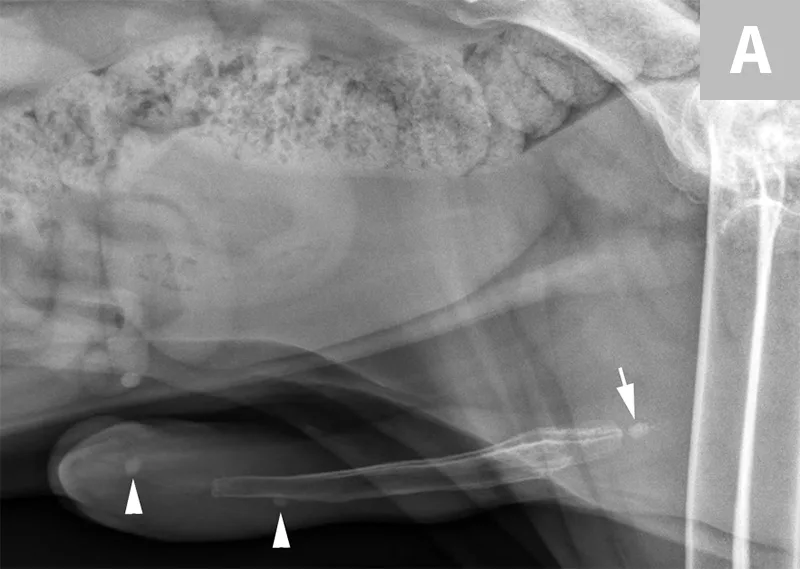

Differentiation between a complete vs partial ureteral obstruction can be difficult with survey radiography and ultrasonography alone. Antegrade pyelography (nephropyelocentesis with renal pelvic injection of iodinated positive contrast medium using ultrasound guidance) may be useful for documenting a complete vs partial obstruction (Figure 7).11

FIGURE 7A

Lateral abdominal radiograph of a cat with multiple, small, oval mineral opacities superimposed over the ventral aspect of the retroperitoneal space (arrows). These mineral opacities are arranged linearly extending from the caudal aspect of the kidneys to the level of the urinary bladder.

Antegrade pyelography is beneficial when compared with standard IV urography, as it lowers the risk of potential contrast-induced renal damage and provides excellent filling of the renal collecting system, regardless of renal function.11